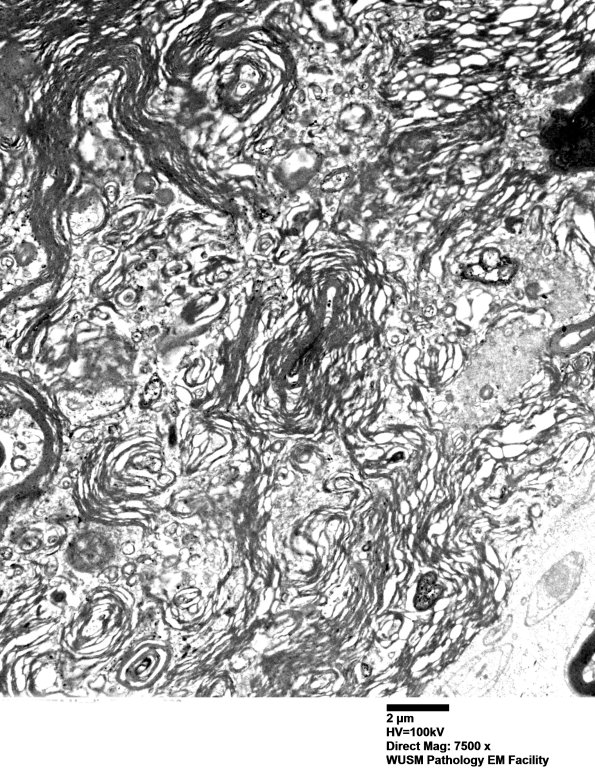

Higher magnification of image #14B1. (electron micrograph)